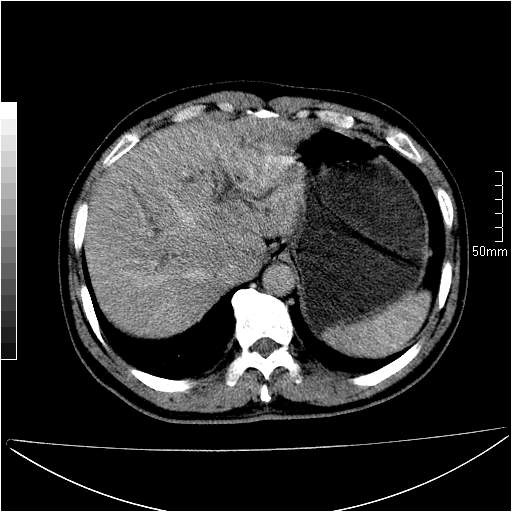

男性,54岁,皮肤黄染,搔痒一周余.b超示肝左叶回声异常.初步诊断1胆总管下段结石2胆囊结石伴慢性胆囊炎请各位战友帮忙看一下肝脏多发低密度如何解释恰当.增强效果不是很好.请大家见谅.

胆总管及肝内胆管扩张,考虑是结石!但,肝内的低密度区增强不明,可能是肝ca,因为肝ca在增强时呈快进快出.另年胆总管扩张原因,可以考虑一下是不是,胆管ca.再次要考虑肝内的低密度是否为海绵状血管瘤所致!

首先,胆总管下端结石梗阻伴肝内胆管扩张可确定。

其次,增强动脉期肝静脉显影,肝实质密度不均。——此为右心功能不全引起肝淤血的表现。

另外,肝八段低密度占位,呈多灶性,考虑肝脓肿或肝癌可能,(图像质量欠佳)建议进一步检查。

由于胆囊窝内结构显示不清,肝脏病灶又邻近胆囊窝首先考虑胆囊癌肝受侵犯。而后因肝脏病灶强化有渐进改变,且相邻胆管扩张,故考虑肝胆管细胞癌待排。

左肝胆管细胞癌。

胆总管下端结石。